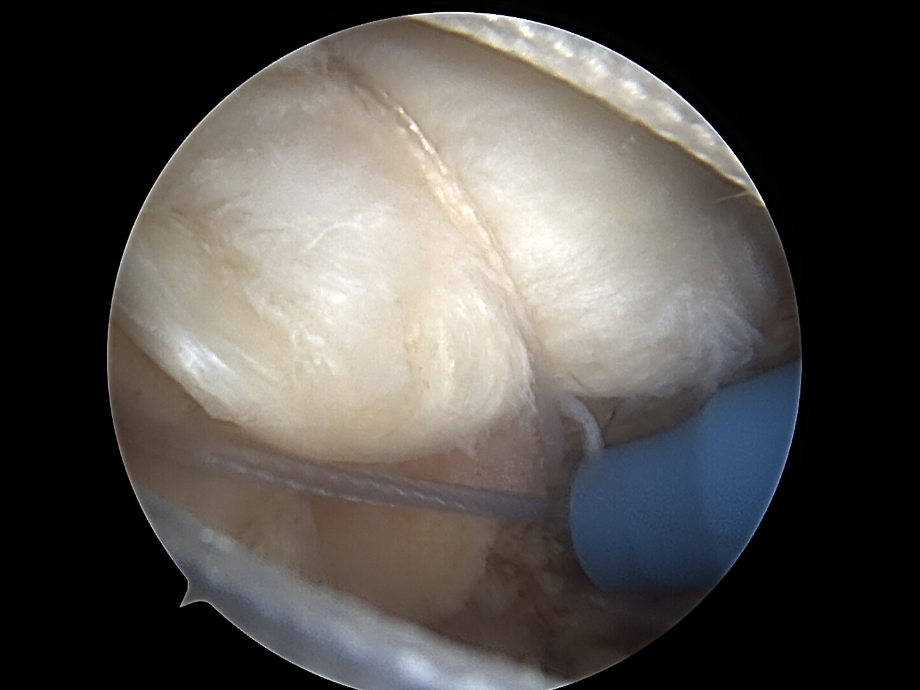

Naht und Refixation

• Verwendung von Fadenankern (Suture Anchors), die im Humeruskopf eingebracht werden. Die Sehne wird mit Fäden durchstochen und zur Knochenoberfläche zurückgeführt.

• Single-Row-Technik: Eine Reihe von Ankern entlang des Footprints.

• Double-Row-Technik: Zwei Reihen für breitere Kontaktfläche (höhere Stabilität).

• Suture-Bridge-Technik: Verbindung beider Reihen

Begleitmaßnahmen und Wundverschluss

• Bei Bedarf: Akromioplastik oder Entfernung von Knochensporn am Acromion.

• Behandlung begleitender Läsionen (z. B. Bizepssehnenpathologie)

• Spülen, Entfernen der Instrumente.

• Hautverschluss (Naht oder Klammern).

• Steriler Verband.